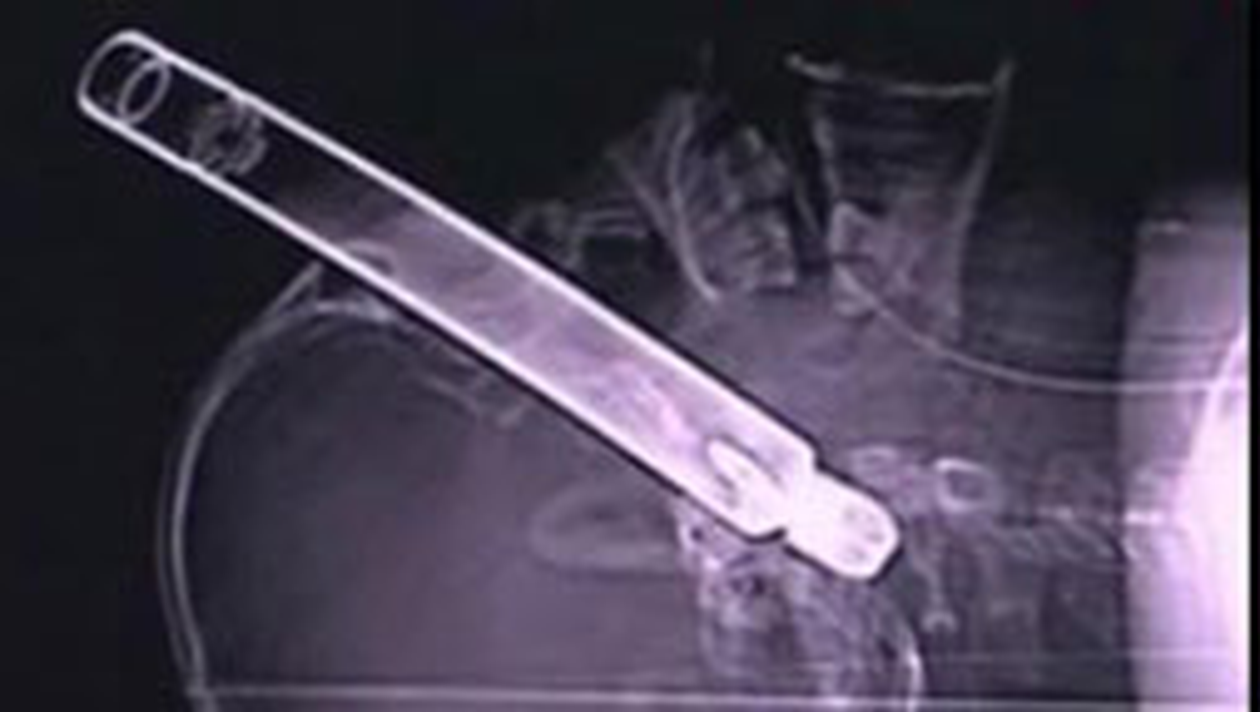

Un barbat de 43 de ani din Brasov a ajuns la spital cu o teava de metal de 30 de centimetri infipta in cap.

Acesta era mecanic auto si a reparat impreuna cu mai multi colegi un utilaj agricol. O piesa s-a desprins din masinarie si i s-a infipt in ochi.Barbatul a fost dus de urgenta la spital. In ciuda eforturilor medicilor, pacientul a decedat pe masa de operatie, din cauza unei hemoragii puternice.